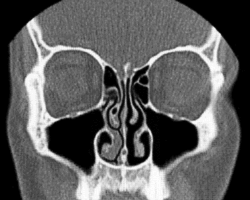

In anatomy, a nasal concha (/ˈkɒnkə/; pl.: conchae; /ˈkɒnk/; Latin for 'shell'), also called a nasal turbinate or turbinal,[1][2] is a long, narrow, curled shelf of bone that protrudes into the breathing passage of the nose in humans and various other animals. The conchae are shaped like an elongated seashell, which gave them their name (Latin concha from Greek κόγχη). A concha is any of the scrolled spongy bones of the nasal passages in vertebrates.[3]

In humans, the conchae divide the nasal airway into four groove-like air passages, and are responsible for forcing inhaled air to flow in a steady, regular pattern around the largest possible surface area of nasal mucosa. As a ciliated mucous membrane with shallow blood supply, the nasal mucosa cleans, humidifies and warms the inhaled air in preparation for the lungs.

Conchae are composed of pseudostratified columnar, ciliated respiratory epithelium with a thick, vascular, and erectile glandular tissue layer.[4] The conchae are located laterally in the nasal cavities, curling medially and downward into the nasal airway. Each pair is composed of one concha in either side of the nasal cavity, divided by the septum.[4]

The superior conchae are smaller structures, connected to the middle conchae by nerve-endings, and serve to protect the olfactory bulb. The superior conchae attach to the ethmoid bone. The openings to the posterior ethmoidal sinuses exist under the superior meatus.[3] The sphenoid sinus ostium exists medial to the superior turbinate.[5]

The middle conchae are smaller but have the most complex anatomy of the nasal turbinates. They originate from the lateral edge of the cribriform plate of the ethmoid bone. They insert anteriorly into the frontal process of the maxilla and posteriorly into the perpendicular plate of the palatine bone.[6] There are three mutually perpendicular segments of the middle turbinate: from proximal to distal, there is the horizontal segment (axial plane), the basal lamella (coronal plane), and the vertical segment (sagittal plane). They project downwards over the openings of the maxillary and anterior and middle ethmoid sinuses, and act as buffers to protect the sinuses from coming in direct contact with pressurized nasal airflow. Most inhaled airflow travels between the inferior concha and the middle meatus.[3] In humans, they are usually as long as the little finger.

The inferior conchae are the largest turbinates, can be as long as the index finger in humans, and are responsible for the majority of airflow direction, humidification, heating, and filtering of air inhaled through the nose.[3]